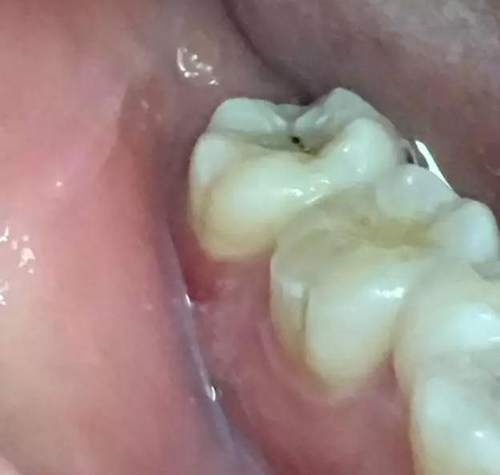

圖1.患者自述右側下后牙牙齦紅腫,咀嚼不適。術前口內(nèi)像:37頰側牙齦紅腫

10.jpg